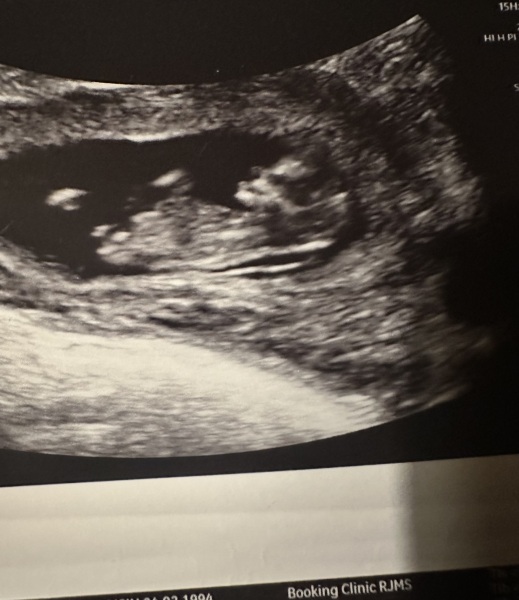

Hi everyone. Worried sick as I went for my booking scan as I am 11 weeks pregnant with my 2nd baby, midwife said Nuchal fold measured 3.8mm but to come back in a weeks time for a rescan as I would be measuring 12 weeks! Then unloaded a lot of information that it could be Down syndrome and told me not to freak out until I have a rescan not really sure how to feel. Have been so upset but feeling like I should just be positive for Fridays rescan that it measures lower? I’ve added a photo of my scan

Nuchal fold measuring 3.8mm at 11 weeks